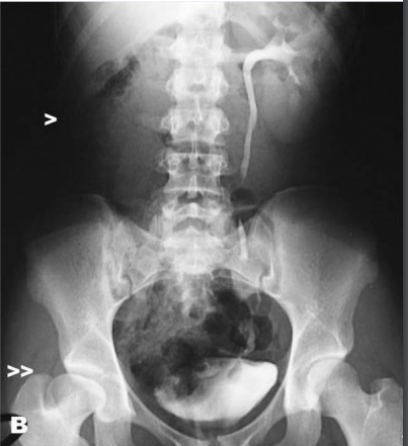

What is this lesion and why are the kidneys susceptable ?

Kidney Infarction